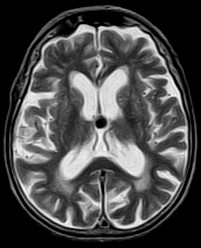

August 2005 - Colloid Cyst

Colloid cysts are benign, epithelial lined lesions, usually located antero-superior to the third ventricle (between the columns of the fornices). They supposedly originate due to an infolding of the neuroepithelium. These cysts may also occur in the choroid plexus of the lateral ventricles, subarachnoid space and brain parenchyma. They comprise approximately 2% of all glial neoplasms. Patients may present with headaches, sudden transient paralysis of both lower extremities, urinary incontinence, personality changes and/or dementia.

• On MRI

• These lesions may be either hypointense or hyperintense on either T1W or T2W images. The variability is due to it's contents. They may contain mucoid material, blood/hemosiderin, macrophages, cholesterol crystals, CSF and various ions (Na, Mg, Ca, Cu, Si, Al, Fe, P).

• Occasionally they may contain serous fluid and follow CSF signal characteristics.

• The lesions are thin walled and peripheral enhancement is common.